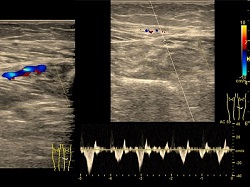

Doppler żył-prawidłowe przepływy.